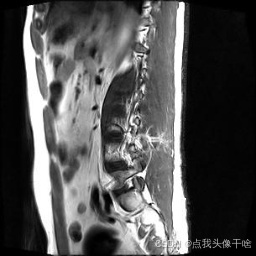

想象一下,你给AI看一张脊椎的核磁共振(MRI)照片,它就能像经验丰富的医生一样,把照片里每一块骨头、每一节椎间盘都给你清清楚楚地标记出来。这个系统干的就是这个酷炫的事儿!

- 原图:就是一张张脊椎的MRI扫描图。